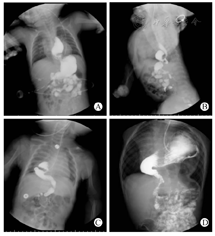

食管裂孔疝在胸部X线片和CT上都有比较特征性的表现,即食管下端和部分胃体疝入纵隔。诊断的金标准是上消化道造影,可见贲门和部分胃组织通过食管裂孔疝入纵隔。在巨大型食管裂孔疝患儿,可见到全胃甚至腹腔内其他脏器组织也一并疝入纵隔(图2)。CT检查可增加对食管裂孔疝诊断的可视性,CT三维重建图像更增加了对食管裂孔疝诊断的敏感性。

食管裂孔疝的Berrott分型[5]根据裂孔缺损位置及疝入组织的多少分为滑动型食管裂孔疝(Ⅰ型)、食管裂孔旁疝(Ⅱ型)、混合型食管裂孔疝(Ⅲ型);也有将裂孔缺损过大导致全胃和肠道、大网膜疝入纵隔的分为巨大型食管裂孔疝(Ⅳ型)[5,6](图1)。新生儿期滑动型食管裂孔疝(Ⅰ型)最为常见(约占70%)[7]。根据分型不同,腹腔段食管、贲门、胃进入胸腔的多少存在差异,其病理生理改变也不相同。